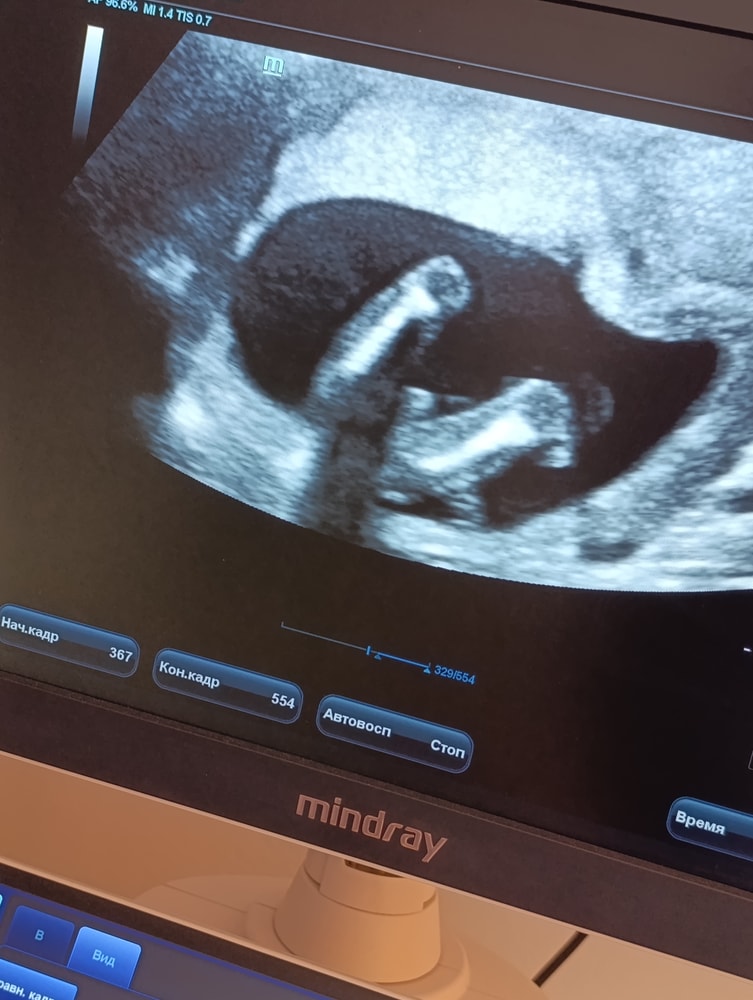

таню, вот и у меня сомнения,два УЗИ в один день,на первом девочка,на втором мальчик.😁